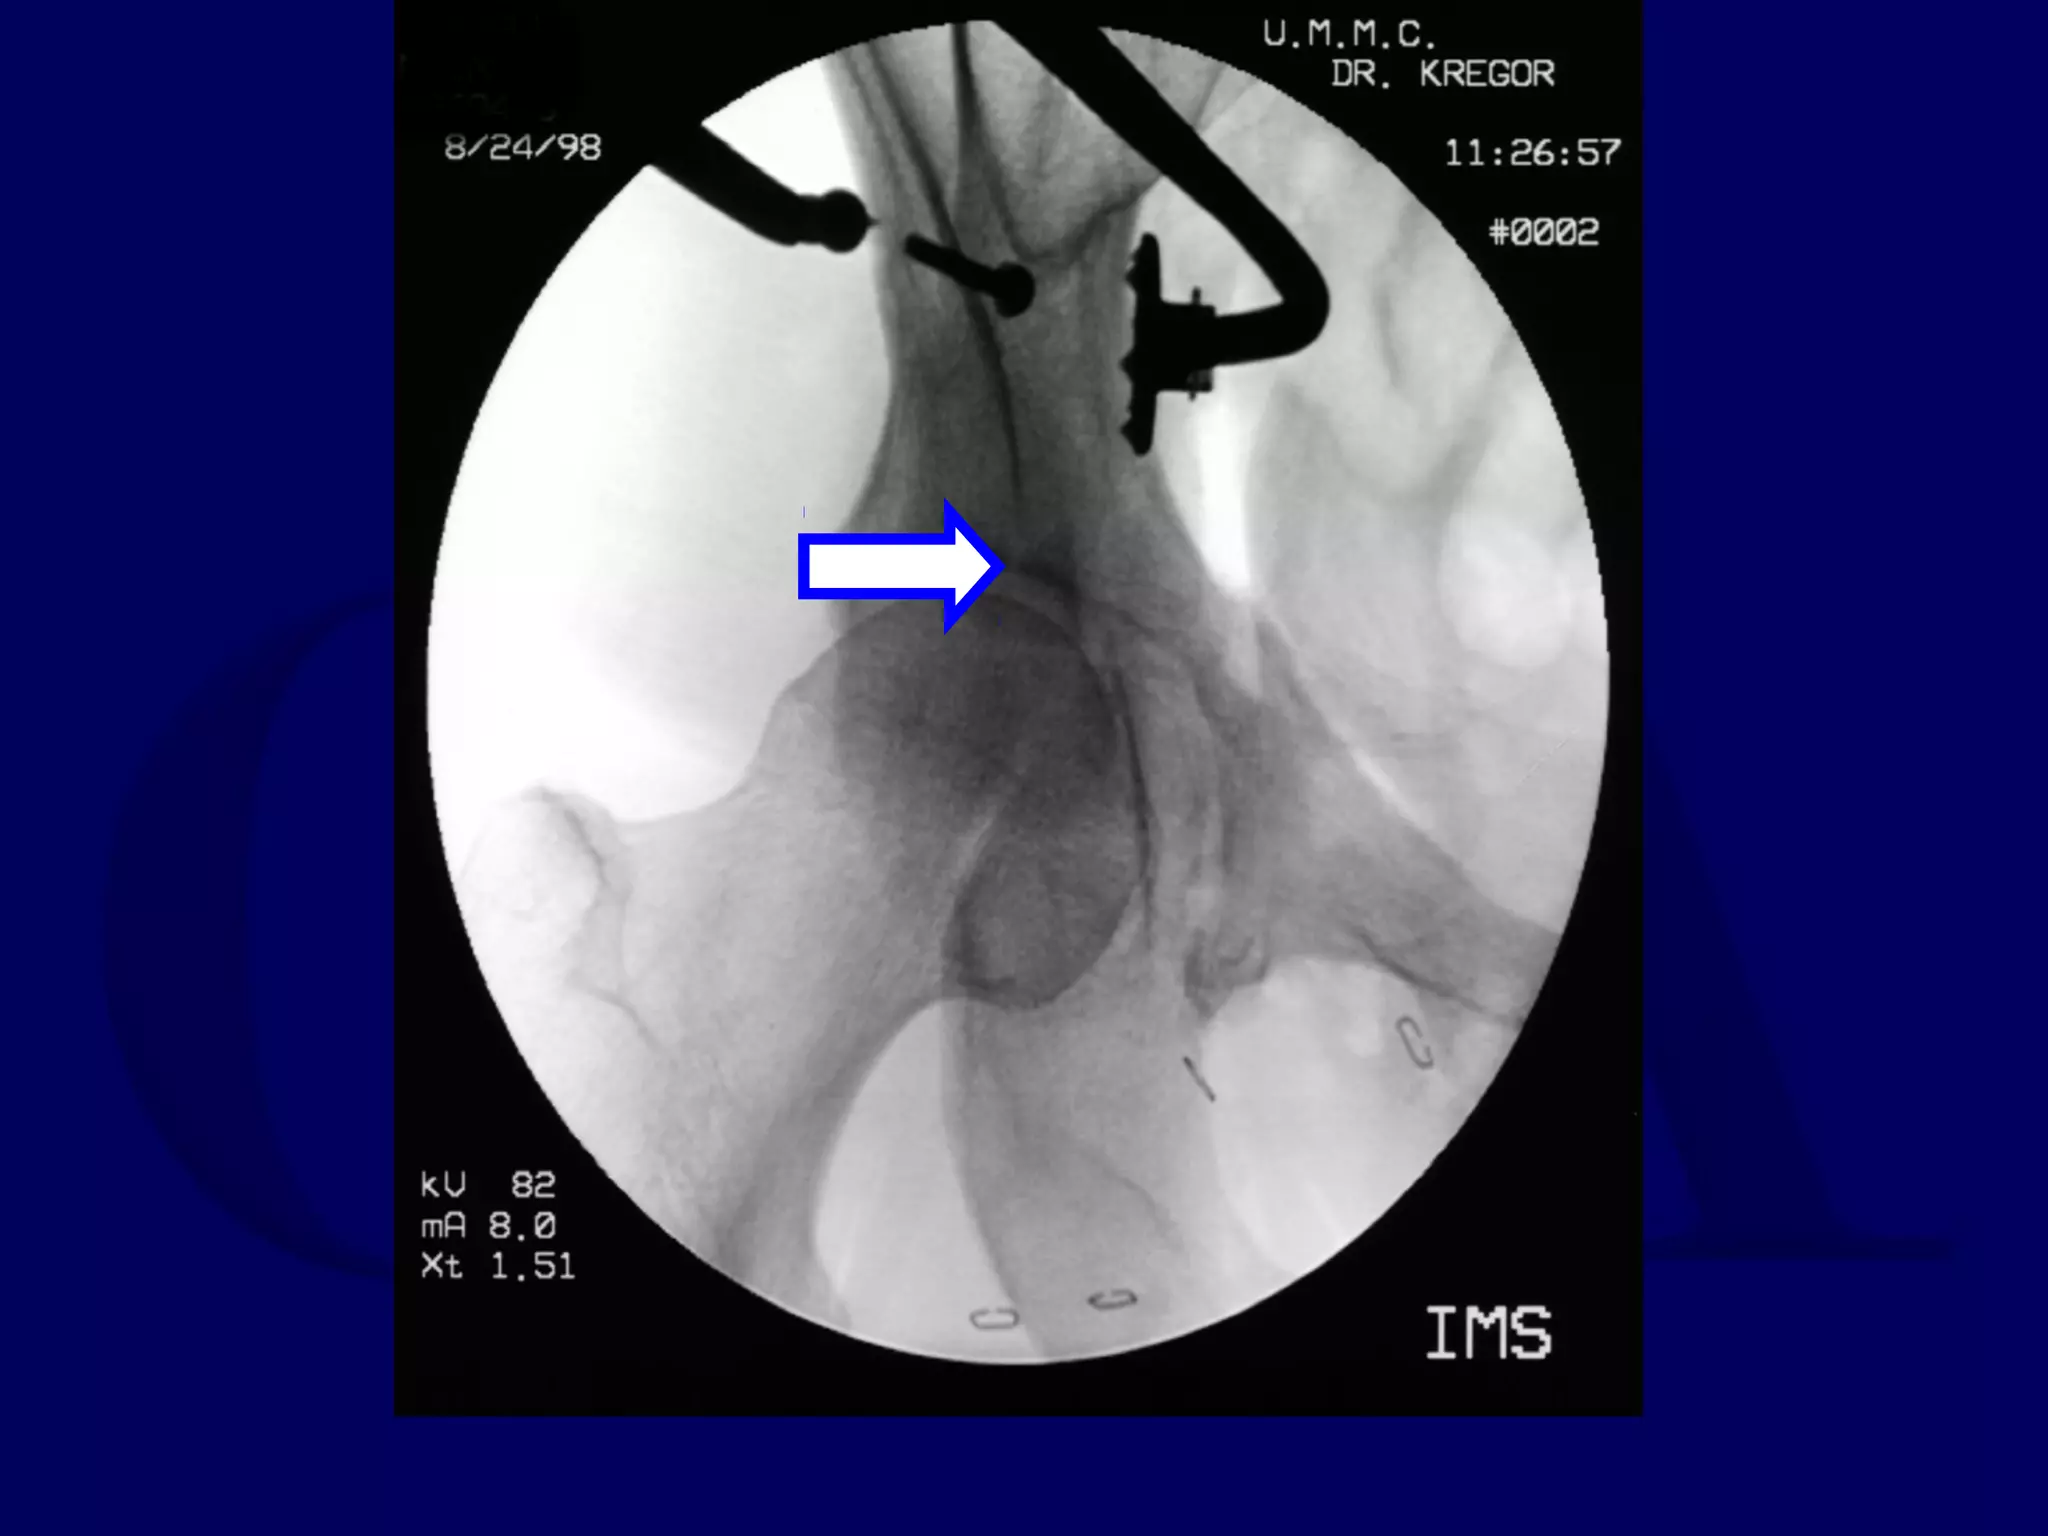

R.M. 98.08.15

R.M. 98.08.24